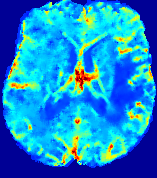

LesionRefer to captionRefer to captionRefer to captionRefer to captionRefer to captionRefer to caption𝐕rgbsubscript𝐕𝑟𝑔𝑏{\bf{V}}_{rgb}Refer to captionRefer to captionRefer to captionRefer to captionRefer to captionRefer to caption𝐕2subscriptnorm𝐕2{\|\bf{V}}\|_{2}Refer to captionRefer to captionRefer to captionRefer to captionRefer to captionRefer to captionRefer to caption3.53.53.52.82.82.82.12.12.11.41.41.40.70.70.70.00.00.0(mm/s)𝑚𝑚𝑠(mm/s)D𝐷DRefer to captionRefer to captionRefer to captionRefer to captionRefer to captionRefer to captionRefer to caption0.0200.0200.0200.0160.0160.0160.0120.0120.0120.0080.0080.0080.0040.0040.0040.0000.0000.000(mm2/s)𝑚superscript𝑚2𝑠(mm^{2}/s)Slice #1Slice #2Slice #3Slice #4Slice #5Slice #6

Figure 4: PIANO feature maps for another patient in the ISLES 2017 training set, where the lesion is located in the right hemisphere. Top row: segmented stroke lesion region (white) on different slices. The corresponding slices for the PIANO feature maps are shown in the following rows.

For a better insight into an estimated velocity field 𝐕𝐕{\bf{V}} and diffusion field 𝐃𝐃{\bf{D}}, we compute the following maps: (1) 𝐕rgbsubscript𝐕𝑟𝑔𝑏{\bf{V}}_{rgb}: Color-coded orientation map of 𝐕=(Vx,Vy,Vz)T𝐕superscriptsuperscript𝑉𝑥superscript𝑉𝑦superscript𝑉𝑧𝑇{\bf{V}}=(V^{x},V^{y},V^{z})^{T}, obtained by normalizing 𝐕𝐕{\bf{V}} to unit length and mapping its 3 components to red, green, blue respectively; (2) 𝐕2subscriptnorm𝐕2\|{\bf{V}}\|_{2}: 222 norm of 𝐕𝐕{\bf{V}}; (3) D𝐷D: scalar field in Eq. 5.

Fig. 3 and Fig. 4 show the PIANO feature maps estimated from two ISLES 2017 patients: all are highly consistent with the lesion in both cases. Details of the blood flow trajectories are revealed in 𝐕rgbsubscript𝐕𝑟𝑔𝑏{\bf{V}}_{rgb} by the ridged patterns and the sharp changes of colors in the unaffected (right) hemisphere, while the flat patterns appearing within the lesion provide little directional information about the velocity and indicate low velocity magnitudes. Velocity magnitudes are more directly visualized via 𝐕2subscriptnorm𝐕2\|{\bf{V}}\|_{2}, from which one can easily locate the lesion where 𝐕2subscriptnorm𝐕2\|{\bf{V}}\|_{2} is low. D𝐷D also indicates lower diffusion values in the lesion, though with less contrast potentially due to the fact that it captures the accumulated effect of CA diffusion at the voxel-level.